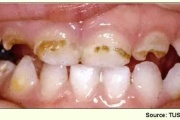

Fluoroos

Fluoroosi

Hammaste defektid